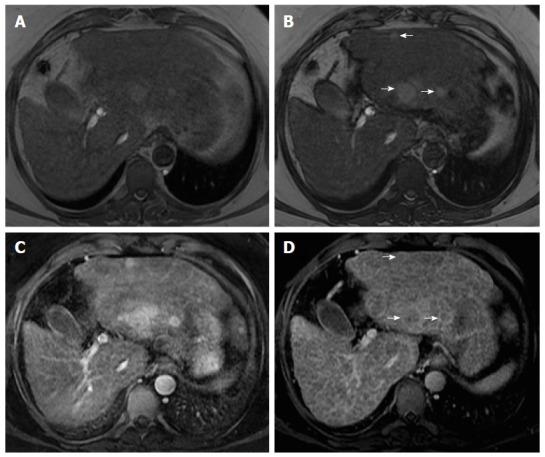

Hepatocellular carcinoma (HCC) usually develops in the setting of chronic liver disease. In the adequate clinical context, both multiphasic contrast-enhanced CT and magnetic resonance imaging are non-invasive modalities that allow accurate diagnosis and staging of HCC, although the latter demonstrates greater sensitivity and specificity. Imaging criteria for HCC diagnosis rely on hemodynamic features such as hyperenhancement in the arterial phase and washout in the portal or equilibrium phase. However, imaging performance drops considerably for small (< 20 mm) nodules because their tendency to exhibit atypical enhancement patterns. In order to improve accuracy in the diagnosis and staging of HCC, particularly in cases of atypical nodules, ancillary features, ., imaging characteristics that modify the likelihood of HCC, have been described and incorporated into clinical reports, especially in Liver Imaging Reporting and Data System. In this paper, ancillary imaging features will be reviewed and illustrated.

肝细胞癌(HCC)通常在慢性肝病背景下发生。在适当的临床背景下,多期对比增强CT和磁共振成像都是非侵入性检查方法,可实现HCC的准确诊断和分期,尽管后者具有更高的敏感性和特异性。HCC诊断的影像学标准依赖于血流动力学特征,如动脉期强化和门脉期或平衡期廓清。然而,对于小(<20mm)结节,其成像表现会显著下降,因为它们倾向于表现出非典型强化模式。为提高HCC诊断和分期的准确性,特别是非典型结节病例,已描述了辅助特征,即改变HCC可能性的影像学特征,并将其纳入临床报告,尤其是肝脏影像报告和数据系统。本文将对辅助影像学特征进行综述和说明。